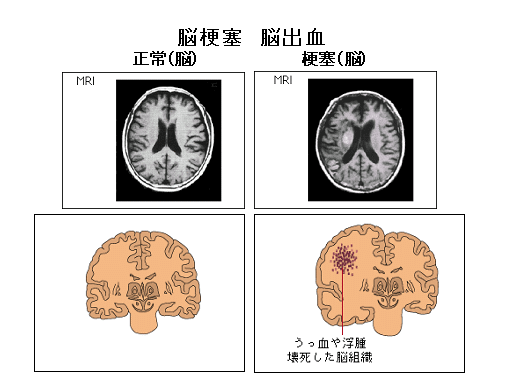

アルツハイマー病の割合は認知症の全体の約半分です。残りの20、30パーセント位が脳梗塞・脳出血からくる認知症です。もう20パーセントぐらいがレビー小体病。5パーセントぐらいがピック病。その他にも効いたことがないかもしれませんが、正常圧水頭症、クロイツフェルト・ヤコブ病、アルコール依存症に伴う認知症などがあります。

脳梗塞・脳出血による痴呆の経過は直線的に悪くなっていくと言うより、脳梗塞が起こるたびに階段状に悪くなっていくことが多いです。